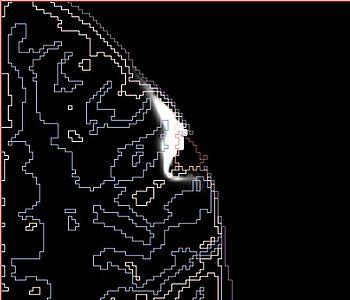

NOTE: red outlines the boundary of the label corresponding to the initial tumor seed!

The following screenshots capture the same axial slice (#119) of the following images in order: (1) image containing the tumor probabilities, and (2) the simulated Gad enhanced image, both overlayed with the warped tumor/brain tissues labels.

Poisson ratio 0.5

(initial value)

Note very very minimal deformation of the surrounding brain tissue, although the tumor volume increased, for Poisson=0.5.